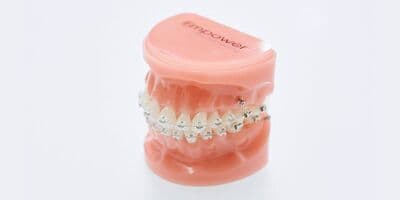

表矯正(ブラケット矯正)

もっとも一般的な治療法です。歯の表面にブラケットという小さな装置を取りつけ、ワイヤーを通して歯を移動させます。幅広い症例に対応し、歯の動きを細かく調整することが可能。金属製のブラケットは目立ちますが、比較的費用を抑えられる点がメリットです。

裏矯正(リンガル矯正)

歯の裏側にブラケットやワイヤーを装着する特殊な技術を使って行う矯正治療です。治療期間中は装置が外から見えないので、お仕事やプライベートでも見た目を気にせずに済みます。仕上がりも、従来のブラケット装置と変わりません。

ハーフリンガル矯正

歯の裏側にブラケットやワイヤーを装着する特殊な技術を使って行う矯正治療です。治療期間中は装置が外から見えないので、お仕事やプライベートでも見た目を気にせずに済みます。仕上がりも、従来のブラケット装置と変わりません。